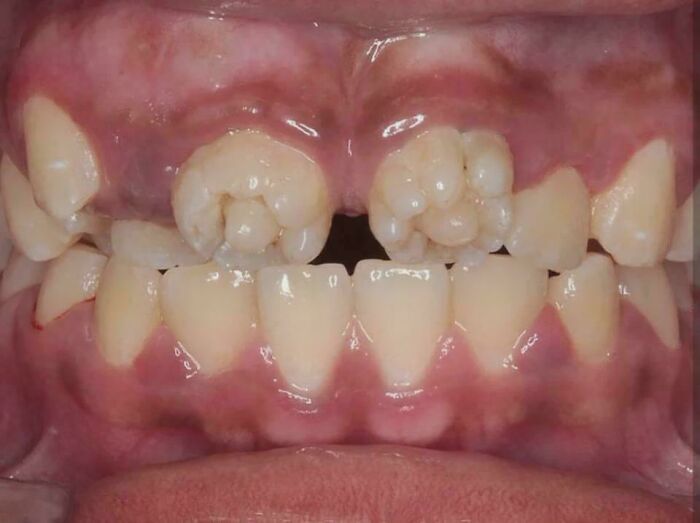

Molarne zmiany typu „morwa” związane z kiłą wrodzoną